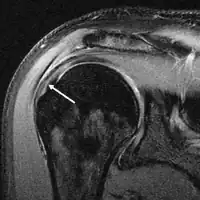

MRI

Magnetic resonance imaging (MRI) and ultrasound[46] are comparable in efficacy and helpful in diagnosis, although both have a false positive rate of 15–20%.[47] MRI can reliably detect most full-thickness tears, although very small pinpoint tears may be missed. In such situations, an MRI combined with an injection of contrast material, an MR-arthrogram, may help to confirm the diagnosis. It should be realized that a normal MRI cannot fully rule out a small tear (a false negative) while partial-thickness tears are not as reliably detected.[48] While MRI is sensitive in identifying tendon degeneration (tendinopathy), it may not reliably distinguish between a degenerative tendon and a partially torn tendon. Again, magnetic resonance arthrography can improve the differentiation.[48] An overall sensitivity of 91% (9% false negative rate) has been reported, indicating that magnetic resonance arthrography is reliable in the detection of partial-thickness rotator cuff tears.[48] However, its routine use is not advised, since it involves entering the joint with a needle, with the potential risk of infection. Consequently, the test is reserved for cases in which the diagnosis remains unclear.